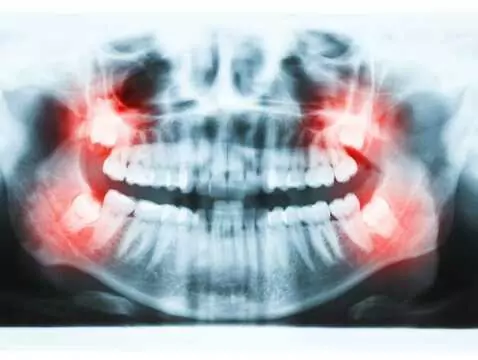

Częste bóle głowy, nieoczekiwane strzykanie w obrębie stawu skroniowo-żuchwowego, uczucie zmęczenia o poranku – to tylko kilka powszechnych dolegliwości, które prędzej powiążemy z niewłaściwą pozycją...

Proste zęby i piękny uśmiech to „miłe skutki uboczne” leczenia ortodontycznego. Dlaczego zatem powinniśmy dbać o zdrowie naszego uzębienia i korygować wadę zgryzu? Na te pytanie odpowiada dr hab. n....

Paradontoza obejmuje 50% dorosłej populacji w świecie z czego 35% ma postać łagodną, a 15% ciężką. Szacuje się, że na paradontozę cierpi 7 na 10 Polaków. Paradontoza jest obecnie znacznie częściej...